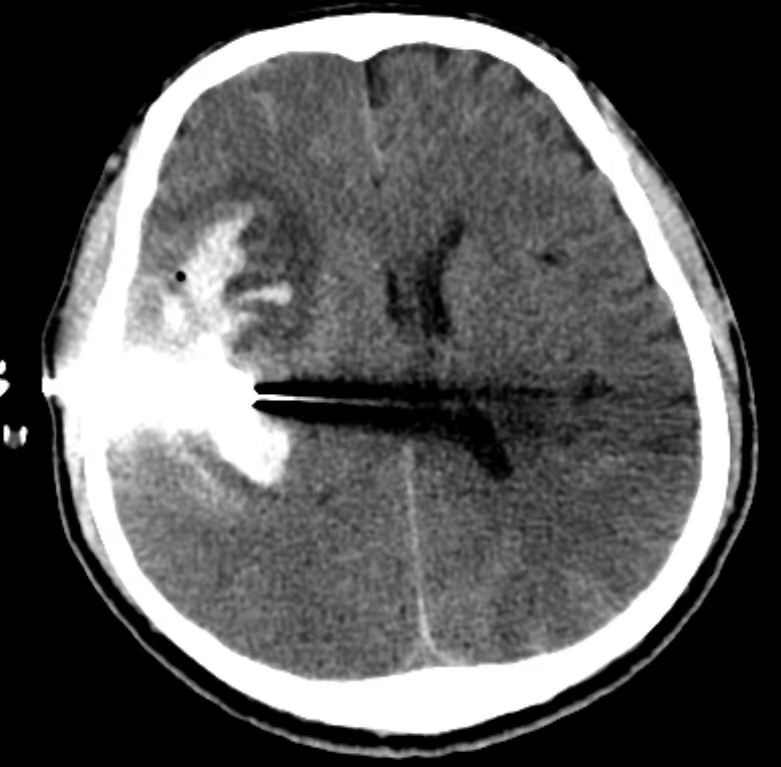

向家属交代病情及治疗方案,家属选择微创介入治疗,拟急诊行动脉瘤栓塞术。术前准备过程中,患者意识障碍加重,呈浅昏迷,双侧瞳孔等大,左侧肢体出现偏瘫。考虑为动脉瘤再次破裂出血,血肿形成。神经外科紧急术前讨论,认为患者病情恶化,二次出血,Hunt-Hess分级达4级,随时有生命危险。再次向家属交代病情及诊治方案,家属仍表示首选微创手术治疗。神经外科决定在复合手术室先行动脉瘤栓塞降低再出血风险,再行硬通道穿刺引流术引流血肿以降低颅内压。

脑血管造影显示右侧大脑中动脉M1段分叉不规则动脉瘤,累及下干,角度刁钻。神经外科副主任医师刘磊决定采用单纯弹簧圈栓塞动脉瘤,避免因支架植入后需口服抗血小板药物进而影响后续的有创手术。经过2小时的手术,动脉瘤达到了致密栓塞,不定时炸弹拆除了,载瘤动脉各分支血流通畅。

术中CT显示右侧颞叶脑内血肿,出血量约50ml。于床旁行硬通道穿刺引流术,当即抽出陈旧血25ml,用时仅15分钟。术后于ICU治疗,病情逐渐好转,术后3周转康复医院继续治疗,出院时患者意识清楚,左侧肢体不全偏瘫。出院后两周患者已行走自如,专程来院送来了感谢信和锦旗。